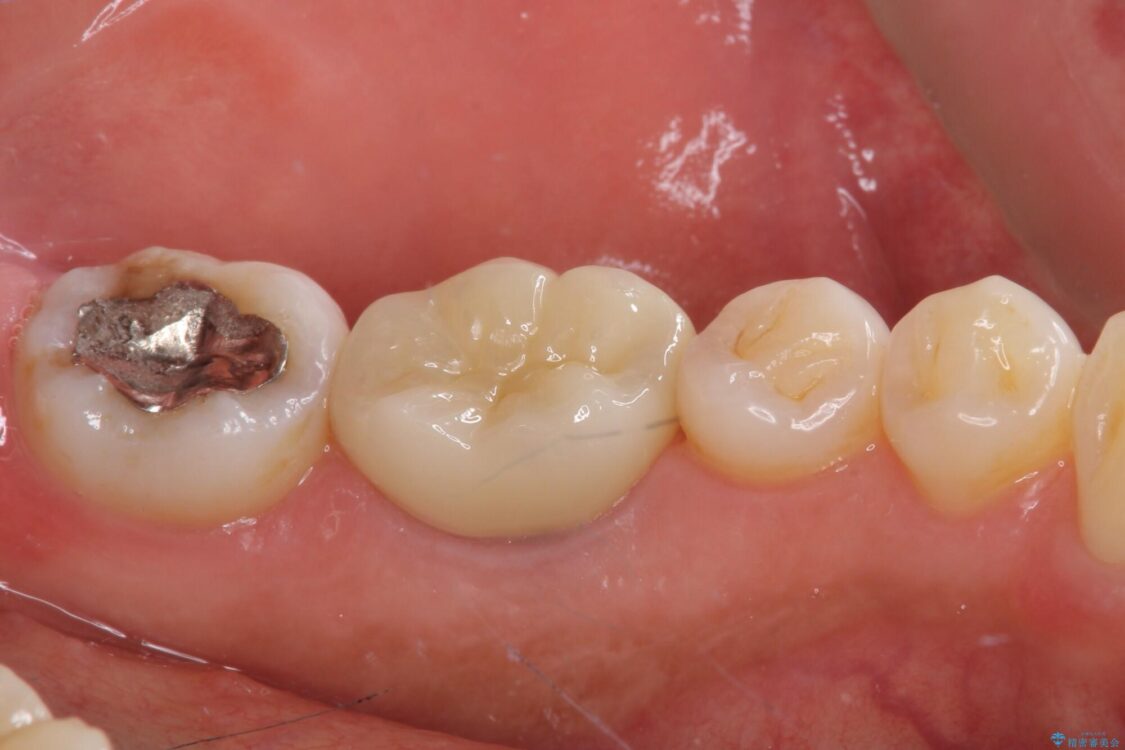

以前むし歯治療をした後から定期的に痛むことがあるとのことで、レントゲン写真より神経組織が失活していることが予想されました。

銀歯を外すと神経組織の一部が取り除かれており、歯根に付け根に穴が空けられている状態でした。

出血の原因は以前の治療で空けられた穴であると考え、封鎖をするとともに根管治療を行い、その後オールセラミッククラウンにて補綴治療を行うこととしました。

治療途中